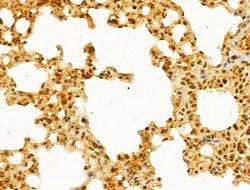

Invitrogen™ GABPB1 Polyclonal Antibody

Antibody detects endogenous levels of total GABPB1.

| Immunohistochemistry (Paraffin), Western Blot, Immunocytochemistry | |

| A synthesized peptide derived from human GABPB1(Accession Q06547), corresponding to amino acid residues V264-D314. | |

| Human, Mouse, Rat | |